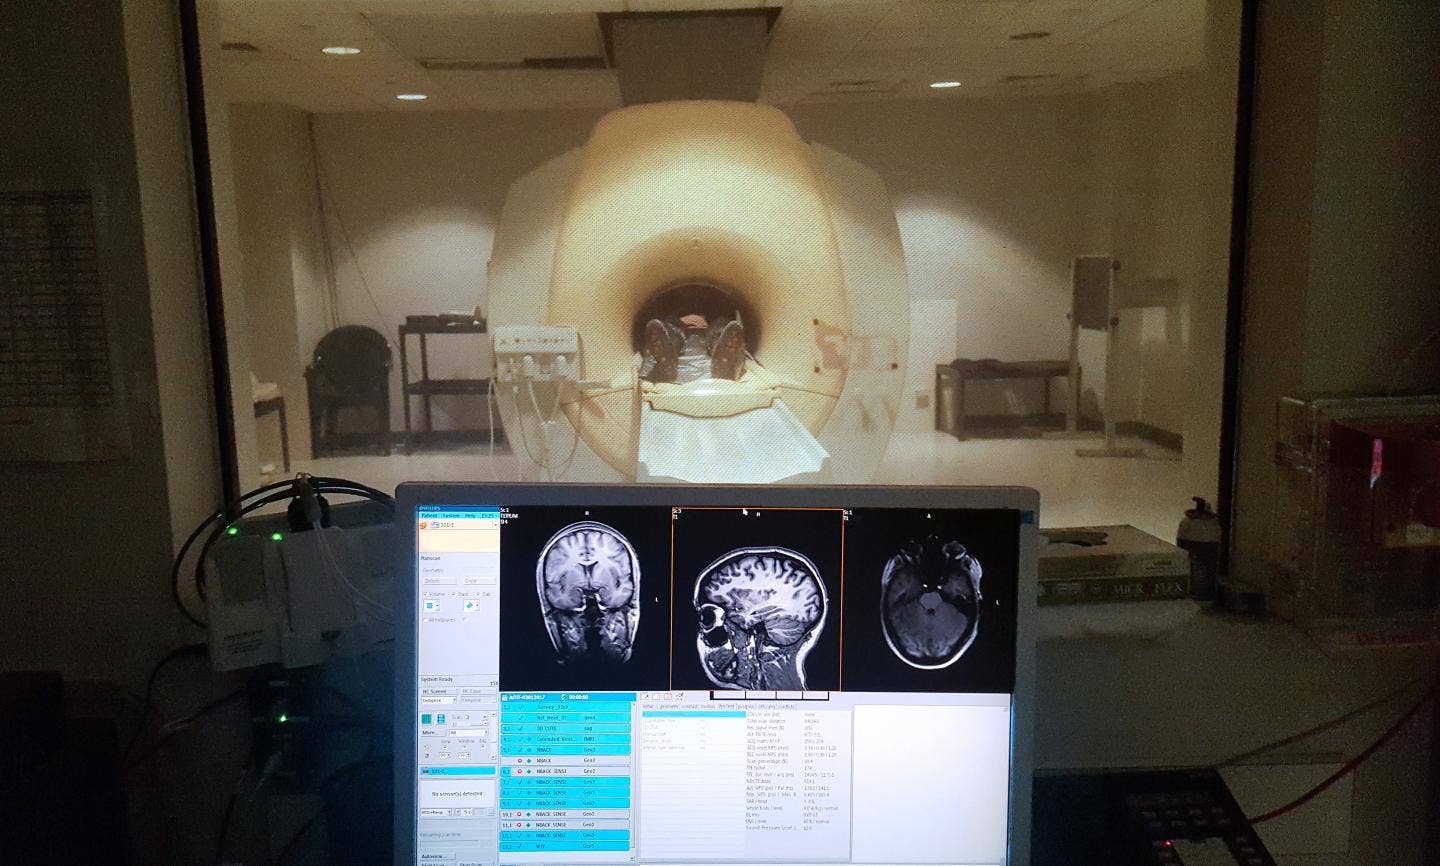

МРТ головного мозга: показания и результаты

Раздел: Визуальный дайджест